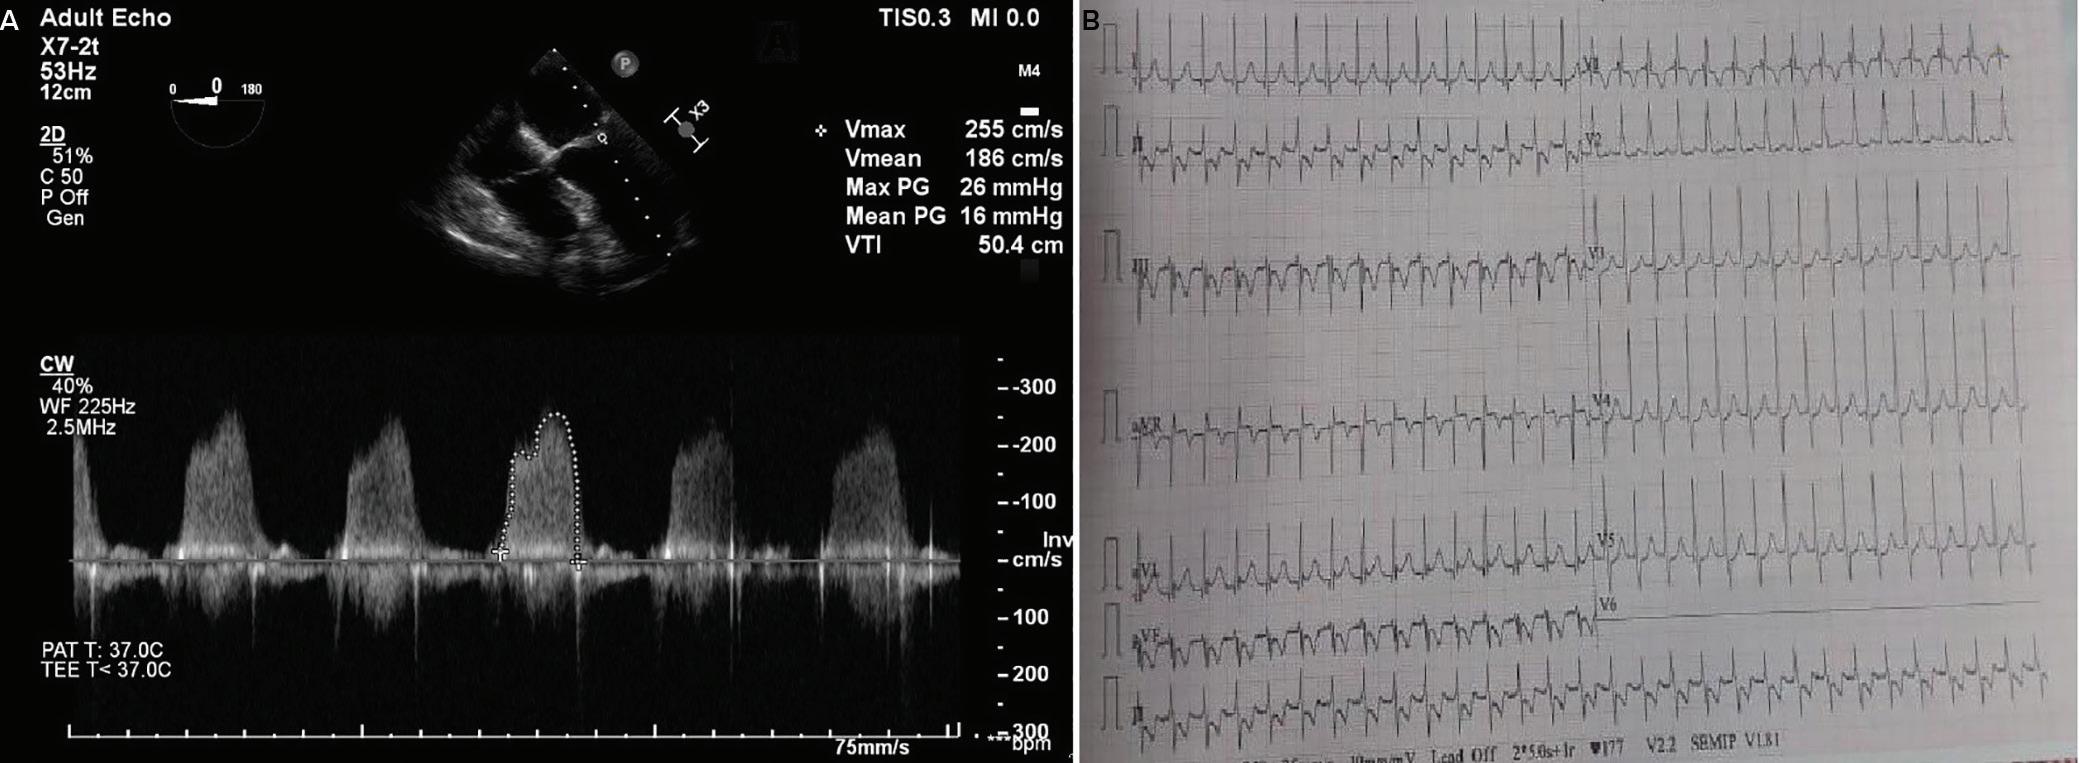

A 57-year-old man presented with a three-decade history of recurrent episodes of palpitation with alarming jugular venous pulsation, but without syncope. Each episode spontaneously reverted to the normal sinus rhythm 6–8 hours after the onset. Cardiac auscultation raised the suspicion of underlying rheumatic mitral stenosis. A 12-lead ECG was suggestive of a WPW pattern with a right posterior septal accessory pathway (Figure 1A). A chest X-ray in the posterior–anterior view was consistent with cardiac auscultation (Figure 1B). A transoesophageal echocardiogram confirmed rheumatic mitral stenosis (Figure 2A and Supplementary Material Video 1). The pliable mitral valve area was 0.8 cm2 and the mean gradient was 17 mmHg at a heart rate of 87 BPM. The coronary angiogram was normal.

The day before the procedure, the patient developed an episode of palpitation during the clinical round. A 12-lead ECG revealed atrial flutter with right bundle branch aberrancy on metoprolol succinate (Figure 2B). The patient’s blood pressure was 124/80 mmHg. Oral verapamil was initiated and the atrial flutter reverted to normal sinus rhythm.

Report confirmed by I II IR aVR V1 V2 V3 V4 V5 V5 aVL aVP A B A: A 12-lead ECG showing the Wolff–Parkinson–White pattern with a possible right posterior septal accessory pathway because the R/S ratio is <0.5 in V1 and V2 and <1 in the inferior leads. B: Chest X-ray in the posterior–anterior view showing mitralisation of the left heart border, double atrial shadow on the right

side and a horizontal left bronchus. A: There was significant mitral stenosis and the mean mitral valve gradient of 16 mmHg prior to the balloon mitral valvotomy. B: Atrial flutter with 2:1 atrioventricular block and right bundle branch aberrancy was evident during the electrophysiological study by pacing the atria with a decapolar catheter in the coronary sinus at cycle length of 200 ms.